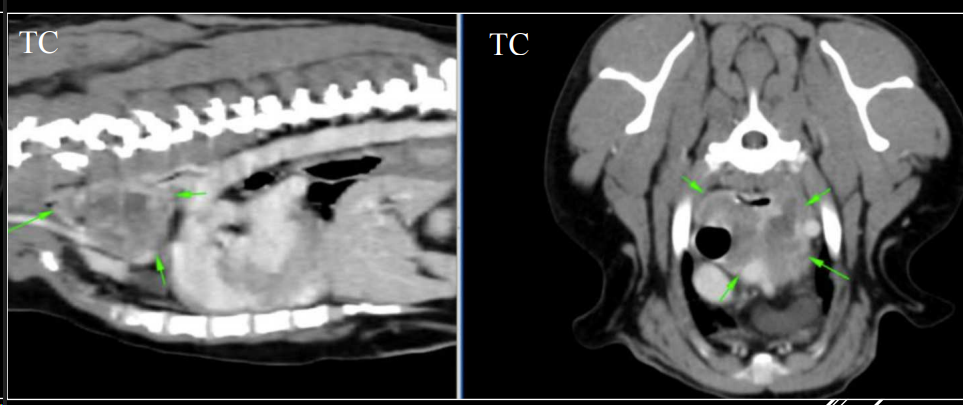

APLICACIONES DEL TC

- Siempre empezamos por una radiografia, ya luego tomogrofia o TC (Al ser mas caro y siendo generalmenta la mayoria de problemas diagnosticables con radiografia)

- Exploraciones radiográficas inconcluyentes.

- Ampliar información de estudios radiográficos.

- Diferenciar entre lesión mediastínica, pulmonar, pleural o pared torácica.

- Detectar metástasis de pequeño tamaño o tromboembolismos pulmonares.

- Evaluar la lesión previo a cirugía.

- Toma de biopsias guiada.

Hiliares/Perihiliares: alteraciones esofágicas, tumor base cardiaca, linfoadenopatía traqueobronquial, masa tiroidea ectópica.

-

Masa de opacidad tejido blando que desplaza la traquea y la bifurcación bronquial.

Puede ser por los nodulos parabronquiales, esofagico o por masa en el pulmón